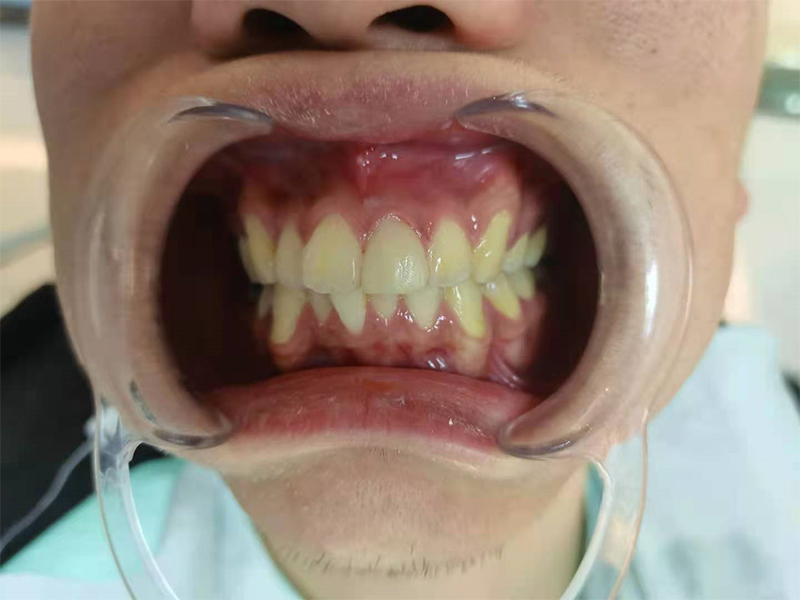

治疗前

检查:21远中切断缺损

治疗方案:瓷贴面修复